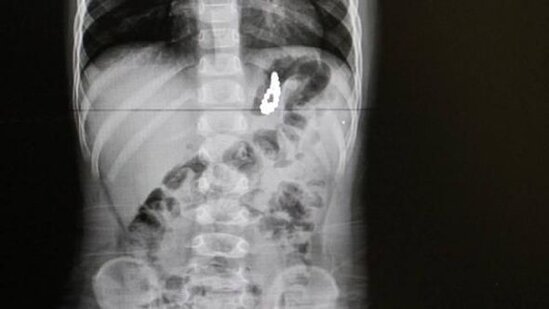

Dənizlidəki Pamukkale universiteti xəstəxanasında 19 aylıq körpə təcili əməliyyat olunub.

Uşağın mədəsindən çıxanlar həkimləri şoka salıb.

Məlum olub ki, balaca Murad oyuncaq kimi istifadə edilən 17 ədəd maqnit muncuq udub.

Həkimlərin sözlərinə görə, maqnitlər uşağın mədəsində bir ay qalıb.

Əməliyyatdan sonra xəstənin səhhətinin normal olduğu bildirilib. Valideynlərə isə daha diqqətli olmaq tövsiyə edilib.\oxu.az